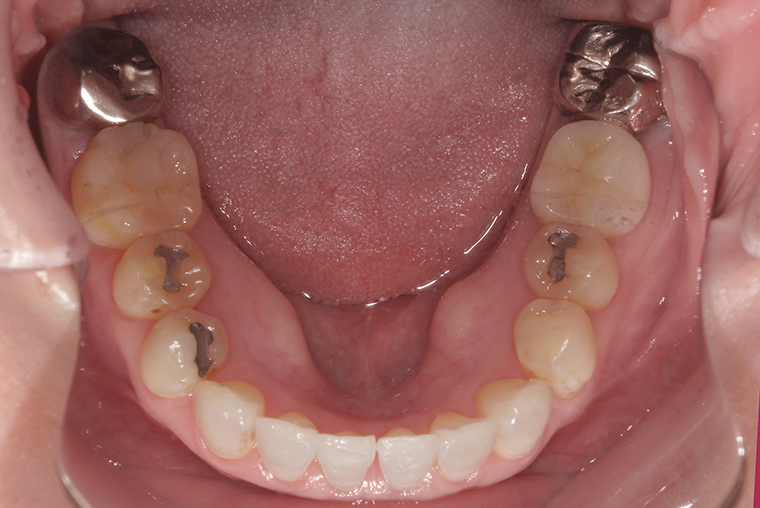

Case Study53歳女性ガタガタな歯のマウスピース矯正-矯正期間1年4ヶ月

BEFORE

AFTER

矯正後は反対の噛み合わせもきれいに整い、見た目もすっきりしました。

思いきって始めて、本当に良かったと感じています。